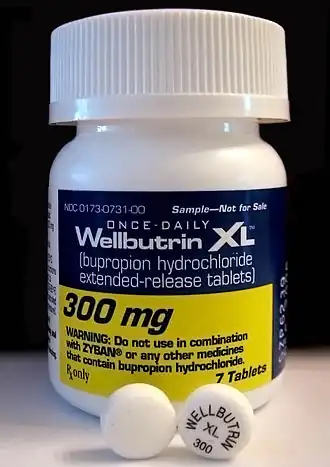

Bupropion, formerly called amfebutamone,[15] and sold under the brand name Wellbutrin among others, is an atypical antidepressant that is indicated in the treatment of major depressive disorder, seasonal affective disorder, and to support smoking cessation.[16][17] It is also popular as an add-on medication in the cases of "incomplete response" to the first-line selective serotonin reuptake inhibitor (SSRI) antidepressant.[17][18] Bupropion has several features that distinguish it from other antidepressants: it does not usually cause sexual dysfunction,[17] it is not associated with weight gain[17] and sleepiness,[19] and it is more effective than SSRIs at improving symptoms of hypersomnia and fatigue.[20] Bupropion, particularly the immediate-release formulation, carries a higher risk of seizure than many other antidepressants; hence, caution is recommended in patients with a history of seizure disorder.[21] The medication is taken by mouth.[2][3]

Bupropion was invented by Nariman Mehta, who worked at Burroughs Wellcome, in 1969.[34] It was first approved for medical use in the United States in 1985.[35] Bupropion was originally called by the generic name amfebutamone, before being renamed in 2000.[15] In 2023, it was the seventeenth most commonly prescribed medication in the United States and the third most common antidepressant, with more than 30 million prescriptions.[36][37] It is on the World Health Organization's List of Essential Medicines.[38] In 2022, the US Food and Drug Administration (FDA) approved the combination dextromethorphan/bupropion to serve as a rapid-acting antidepressant in patients with major depressive disorder.[39]

Available forms

In 1996, the US Food and Drug Administration (FDA) approved a sustained-release formulation of alcohol-resistant bupropion called Wellbutrin SR, a tablet intended to be taken twice a day (as compared with three times a day for immediate-release Wellbutrin).[183] In 2003, the FDA approved another sustained-release formulation called Wellbutrin XL, a hard-shelled tablet intended for once-daily dosing.[184] Wellbutrin SR and XL are available in generic form in the United States and Canada. In 1997, bupropion was approved by the FDA for use as a smoking cessation aid under the name Zyban.[185][183] In 2006, Wellbutrin XL was similarly approved as a treatment for seasonal affective disorder.[186][187]